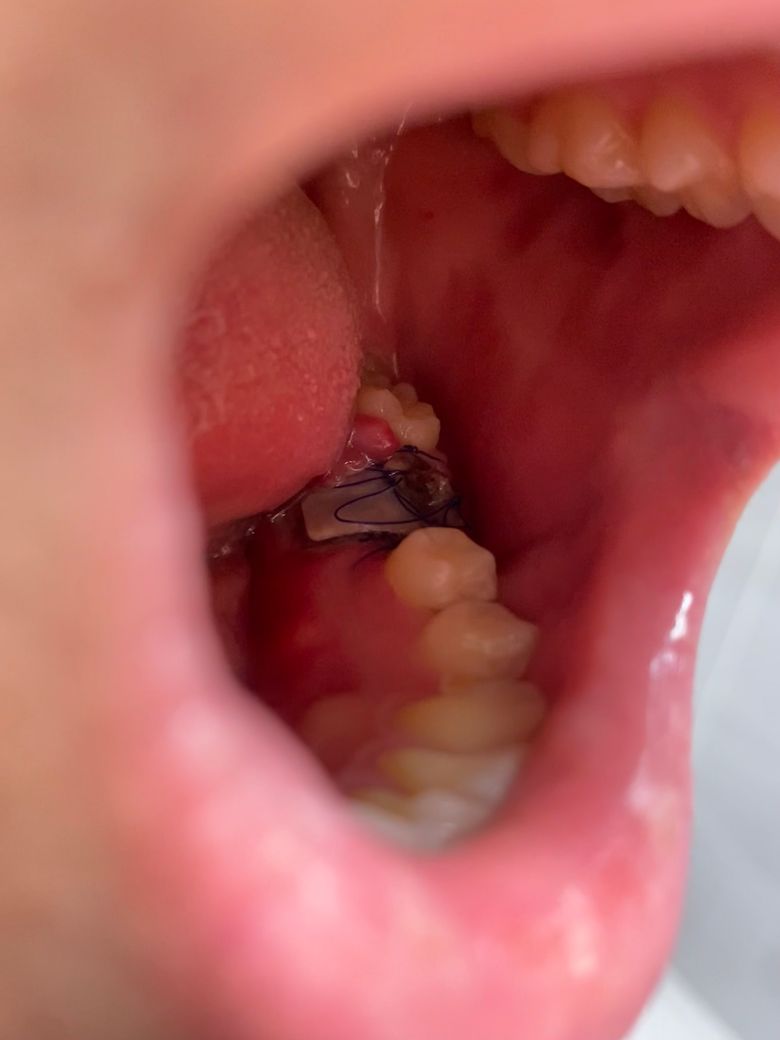

• 2번 째 사진

하얗게 보이는 것은 아마도 뼈이식후 넣은 인조골막이 약간 삐져 나온 것으로 보입니다. 이런 경우 빨리 치과에 가서 실밥 풀고 다른 조치해야 합니다.